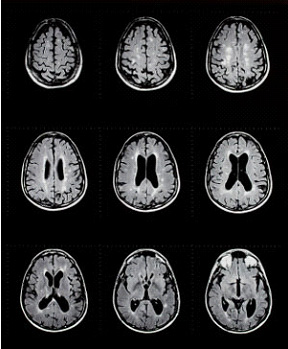

圖片源于網(wǎng)絡(luò)

多發(fā)性硬化是一種慢性疾病,侵犯中樞神經(jīng)系統(tǒng)(脊髓,視神經(jīng)和腦)。常見(jiàn)癥狀是肢體麻木,更嚴(yán)重比例會(huì)出現(xiàn)癱瘓和失明。根據(jù)多發(fā)性硬化癥基金會(huì)的數(shù)據(jù),現(xiàn)有350,000~500,000確診病例,每周有200人被診斷為多發(fā)性硬化癥。